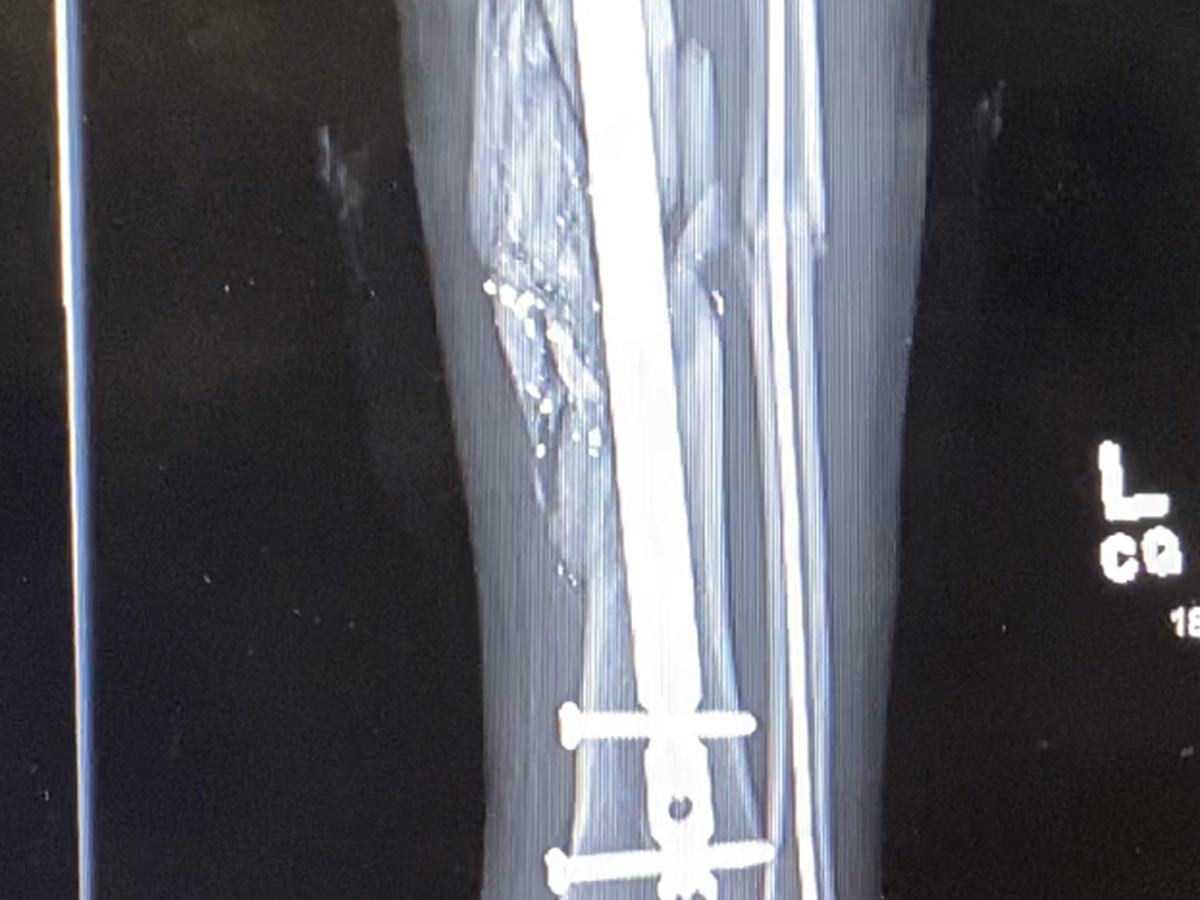

Hey I Am Anthony Garza i got Shot back in 2022 of Aug I saved my Dad From getting Robbed right before my Extern to Help People Out in a Hospital now I am a Patient Suffering in Pain ….Im Not Asking for Much but to Cover some Medical Bills